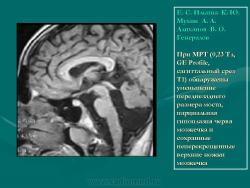

При МРТ (0,23 Тл, GE Profile, сагиттальный срез Т1) обнаружены уменьшение переднезаднего размера моста, парциальная гипоплазия червя мозжечка и сохранные неперекрещенные верхние ножки мозжечка.